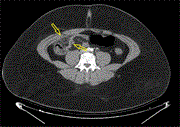

An unusual case of an extensive post-injection retroperitoneal abscess in an intravenous drug user

Georgios Gerasopoulos and others

Journal of Surgical Case Reports, Volume 2024, Issue 6, June 2024, rjae398, https://doi.org/10.1093/jscr/rjae398